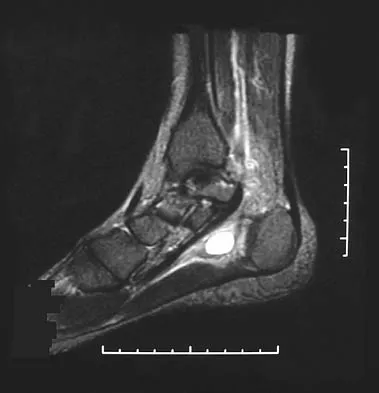

A 37-year-old woman has had intermittent paresthesias and numbness in the plantar foot for the past 6 months. She reports that the symptoms are worse with activity, and the paresthesias are beginning to awaken her at night. MRI scans are shown in Figures 6a and 6b. What is the most likely diagnosis?

The symptoms are consistent with tarsal tunnel syndrome. Ganglion cysts are a well-known cause of tarsal tunnel syndrome. The MRI scans show a high intensity, well-circumscribed mass in the tarsal tunnel that is consistent with a fluid-filled cyst. Patients usually respond well to excision of the ganglion and resolution of the tarsal tunnel symptoms. The surrounding fat is a different signal intensity on the MRI scans, which rules out a lipoma. Synovial cell sarcoma has a heterogeneous appearance on an MRI scan. Metastatic tumors are most commonly found in the osseous structures of the foot, not the soft tissues. Rozbruch SR, Chang V, Bohne WH, et al: Ganglion cysts of the lower extremity: An analysis of 54 cases and review of the literature. Orthopedics 1998;21:141-148. Llauger J, Palmer J, Monill JM, et al: MR imaging of benign soft-tissue masses of the foot and ankle. Radiographics 1998;18:1481-1498.